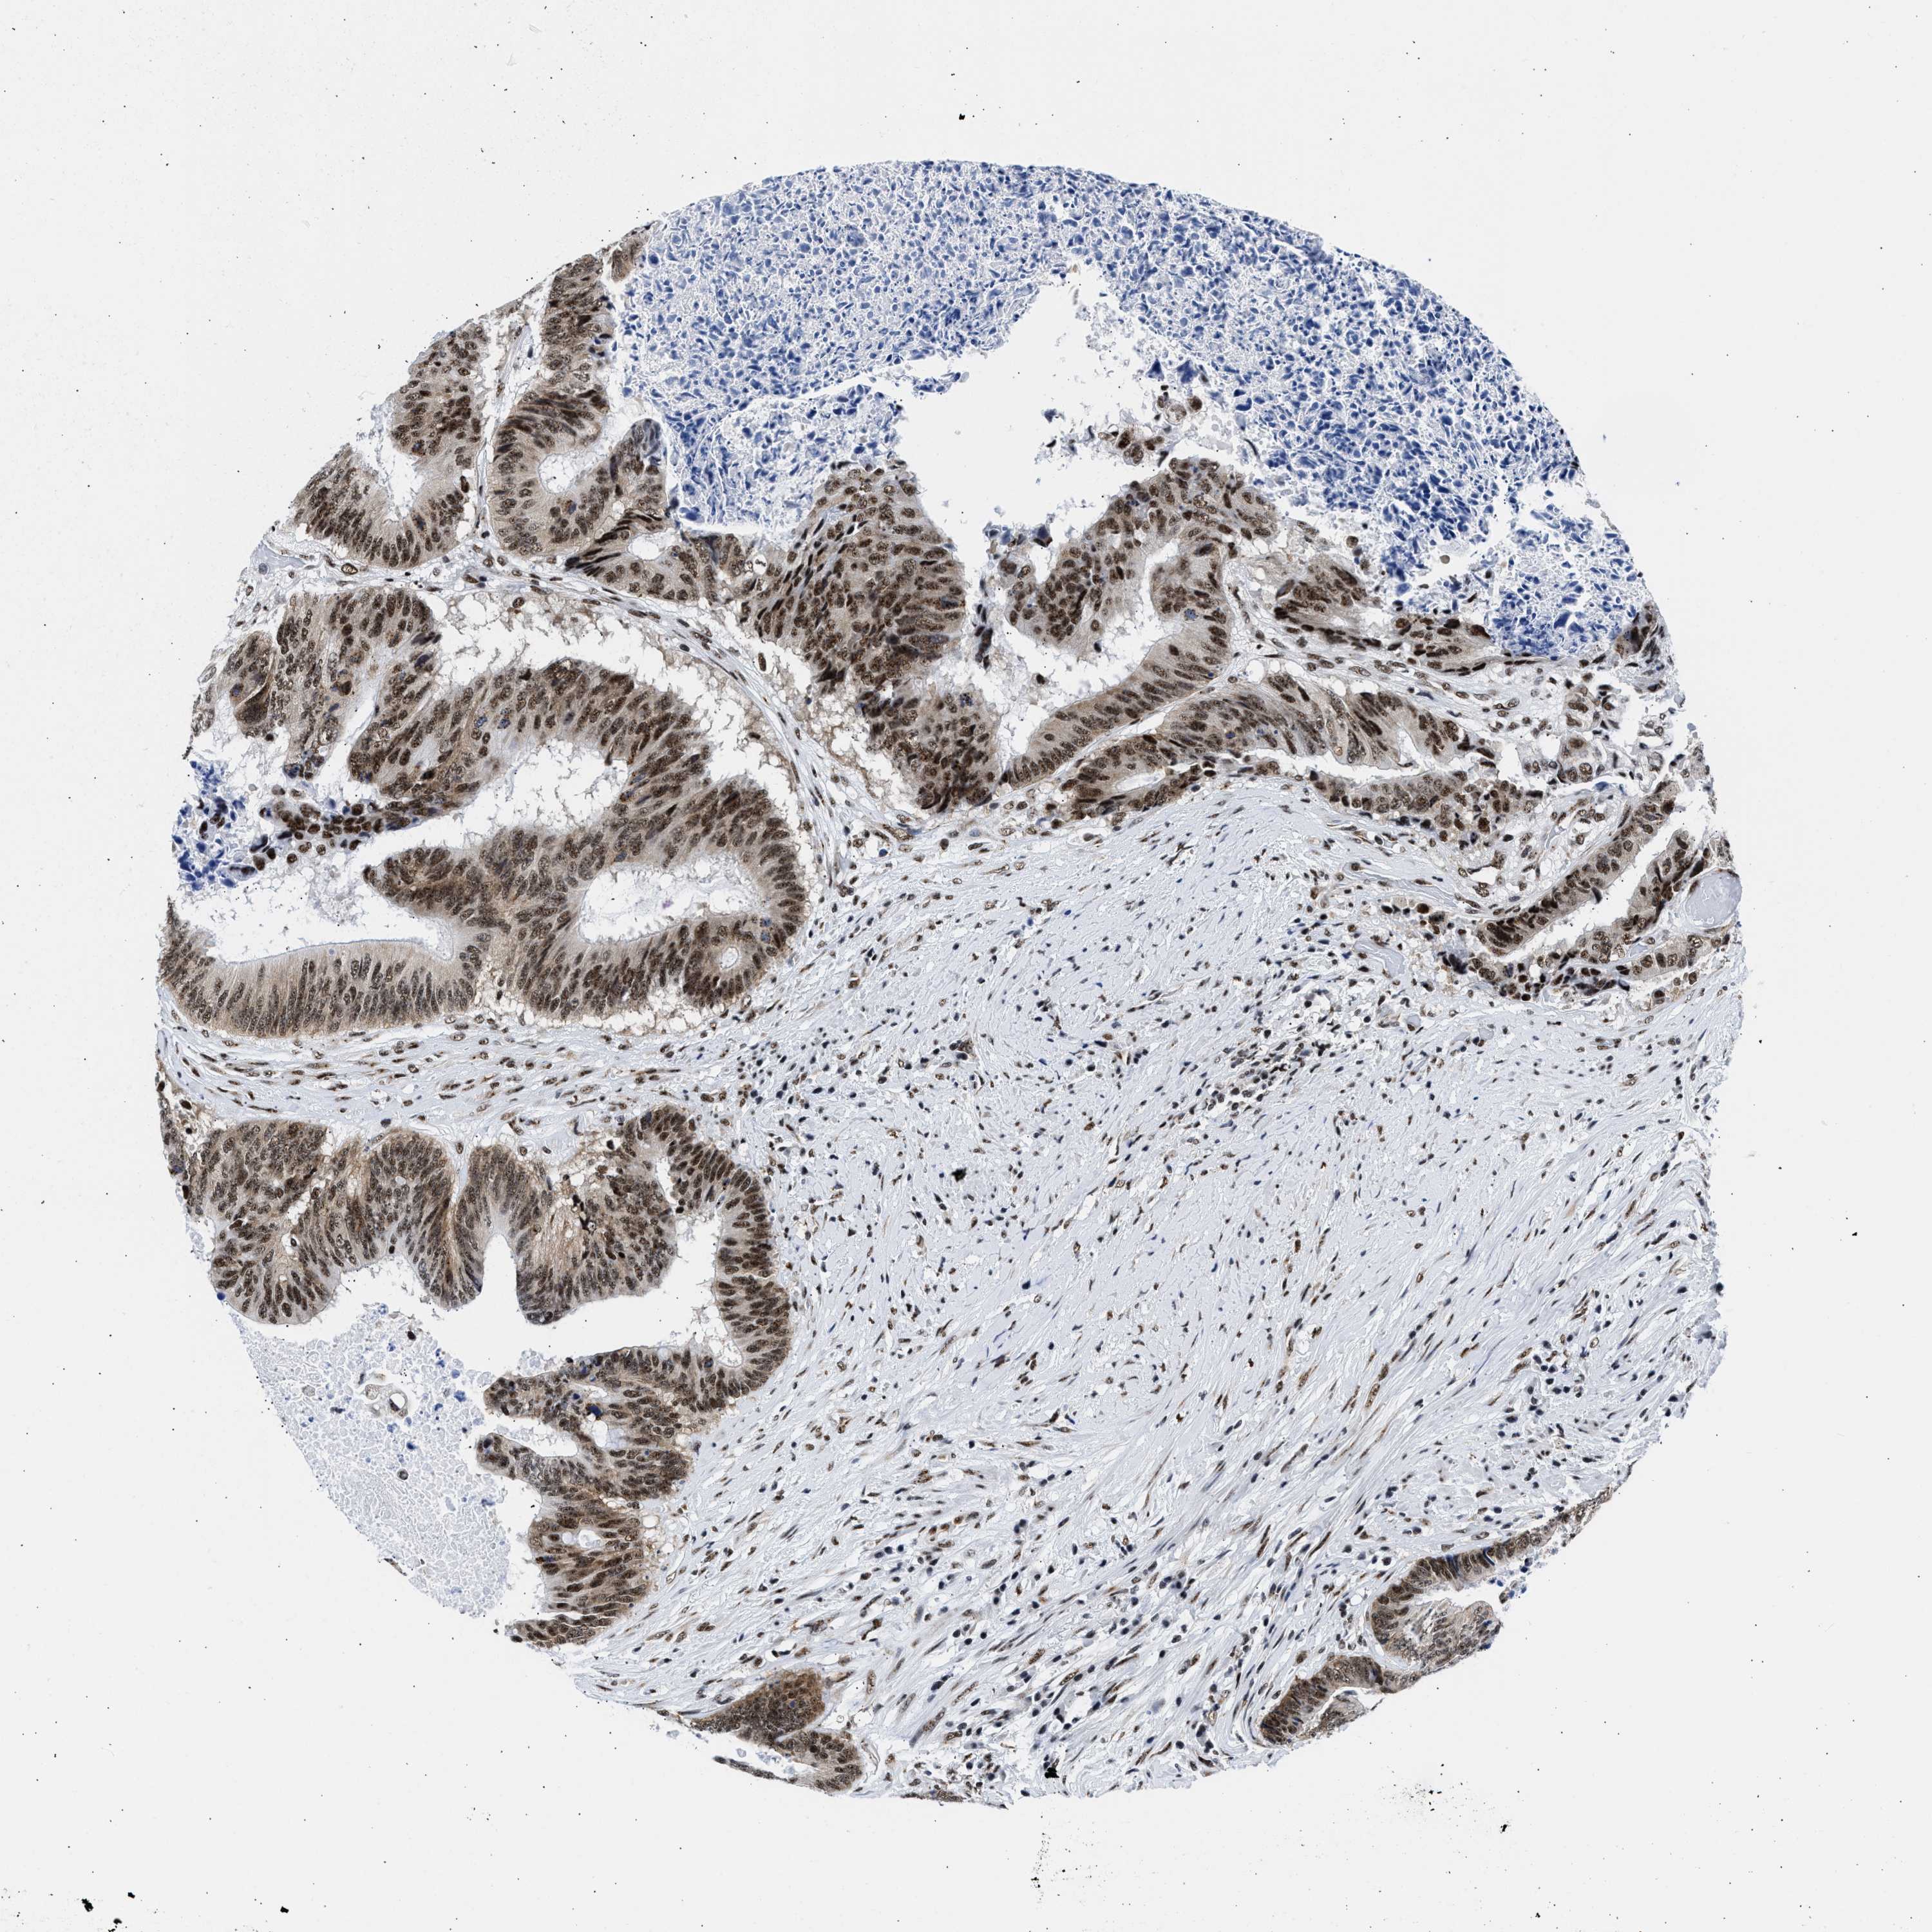

CANCER COLORECTAL CANCER Show tissue menu

Colorectal cancer

Human cancer

Colon adenocarcinoma